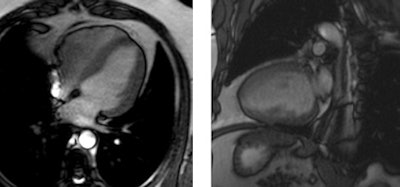

Cardiac magnetic resonance end-diastolic images in the four- and two-chamber view of a subject with cocaine addiction. Concentric left ventricular hypertrophy can be seen, with a quantified left ventricular mass index of 103g/m². Images courtesy of Dr. Alicia Maceira."Cardiovascular MR at 3 tesla detected cardiovascular disease of variable degree in 69% of this cohort of consecutive cocaine abusers," Maceira concluded. "The main findings were a disease in systolic function of both left and right ventricles, an increase of left ventricular mass, and the presence of myocardial late gadolinium enhancement, suggestive of past myocarditis."